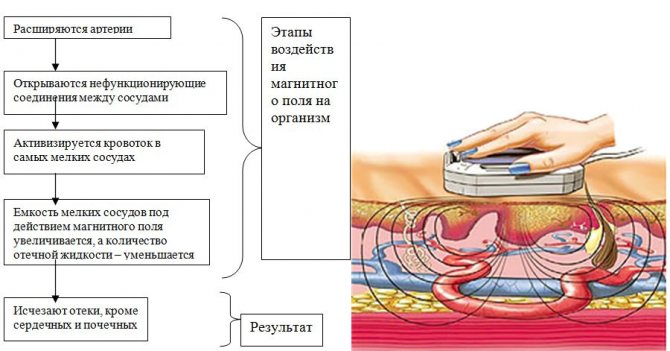

Физиотерапия

Электрический ток низкой частоты при электрофорезе повышает биодоступность лекарств. При процедуре стимулируются обменные процессы в пораженных тканях, ускоряется кровоток, увеличивается кровенаполнение сосудов в области грыжи. В результате происходит ускоренный вывод токсинов, уходит боль. Магнитные поля при магнитотерапии позволяют улучшить кровоснабжение, ускорить обменные процессы, включить компенсаторные механизмы.